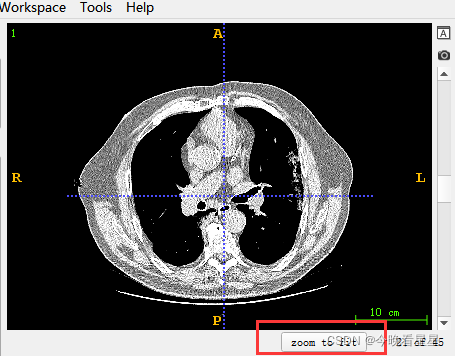

常用的有轴向面与冠状面,可以帮助我们进行空间上的定位与标注

Zoom对区域进行缩放Layer处理添加的不同的层,比如:CT扫描的不同段Slice Annotations -> Toggle....可以去掉视图的标注信息,Slice Annotations -> Annotation Preference可以对标注的格式进行设置